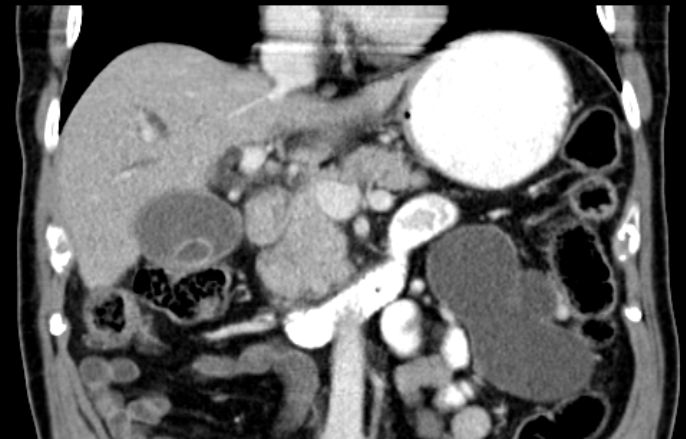

Das CT zeigt im Coronarschnitt den klobigen

Pankreaskopf..![]() |